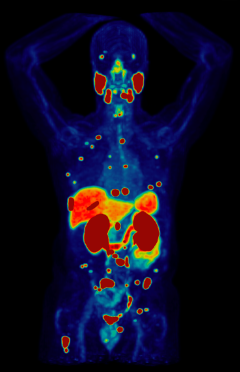

Theranostics is a breakthrough precision medicine approach. By combining targeted imaging (PET scan) with targeted therapy (radionuclide therapy) using the same molecular target, it treats certain types of advanced cancer.

Certain radioisotopes emit radiation which is not harmful to cells and can be imaged using positron emission tomography (PET). This is the diagnostic part of theranostics. Others emit radiation which can damage and even kill cells. This is the therapeutic part.

In theranostics, doctors administer a specialized molecule called a radiotracer that can hold a radioisotope and target cancer cells. The radiotracer then binds to the cancer, allowing doctors to see exactly where it is and deliver cell-damaging radiation directly to it. This “see what you treat” approach helps doctors diagnose, stage, and treat cancer while minimizing damage to healthy tissues.

• Diagnostic Phase: To see where the cancer is, an imaging radiotracer will be administered by your health care team in our outpatient clinic. You will then undergo a full-body PET scan which will create pictures showing where the radiotracer goes. The whole process typically takes less than 3 hours, after which you can leave the clinic.